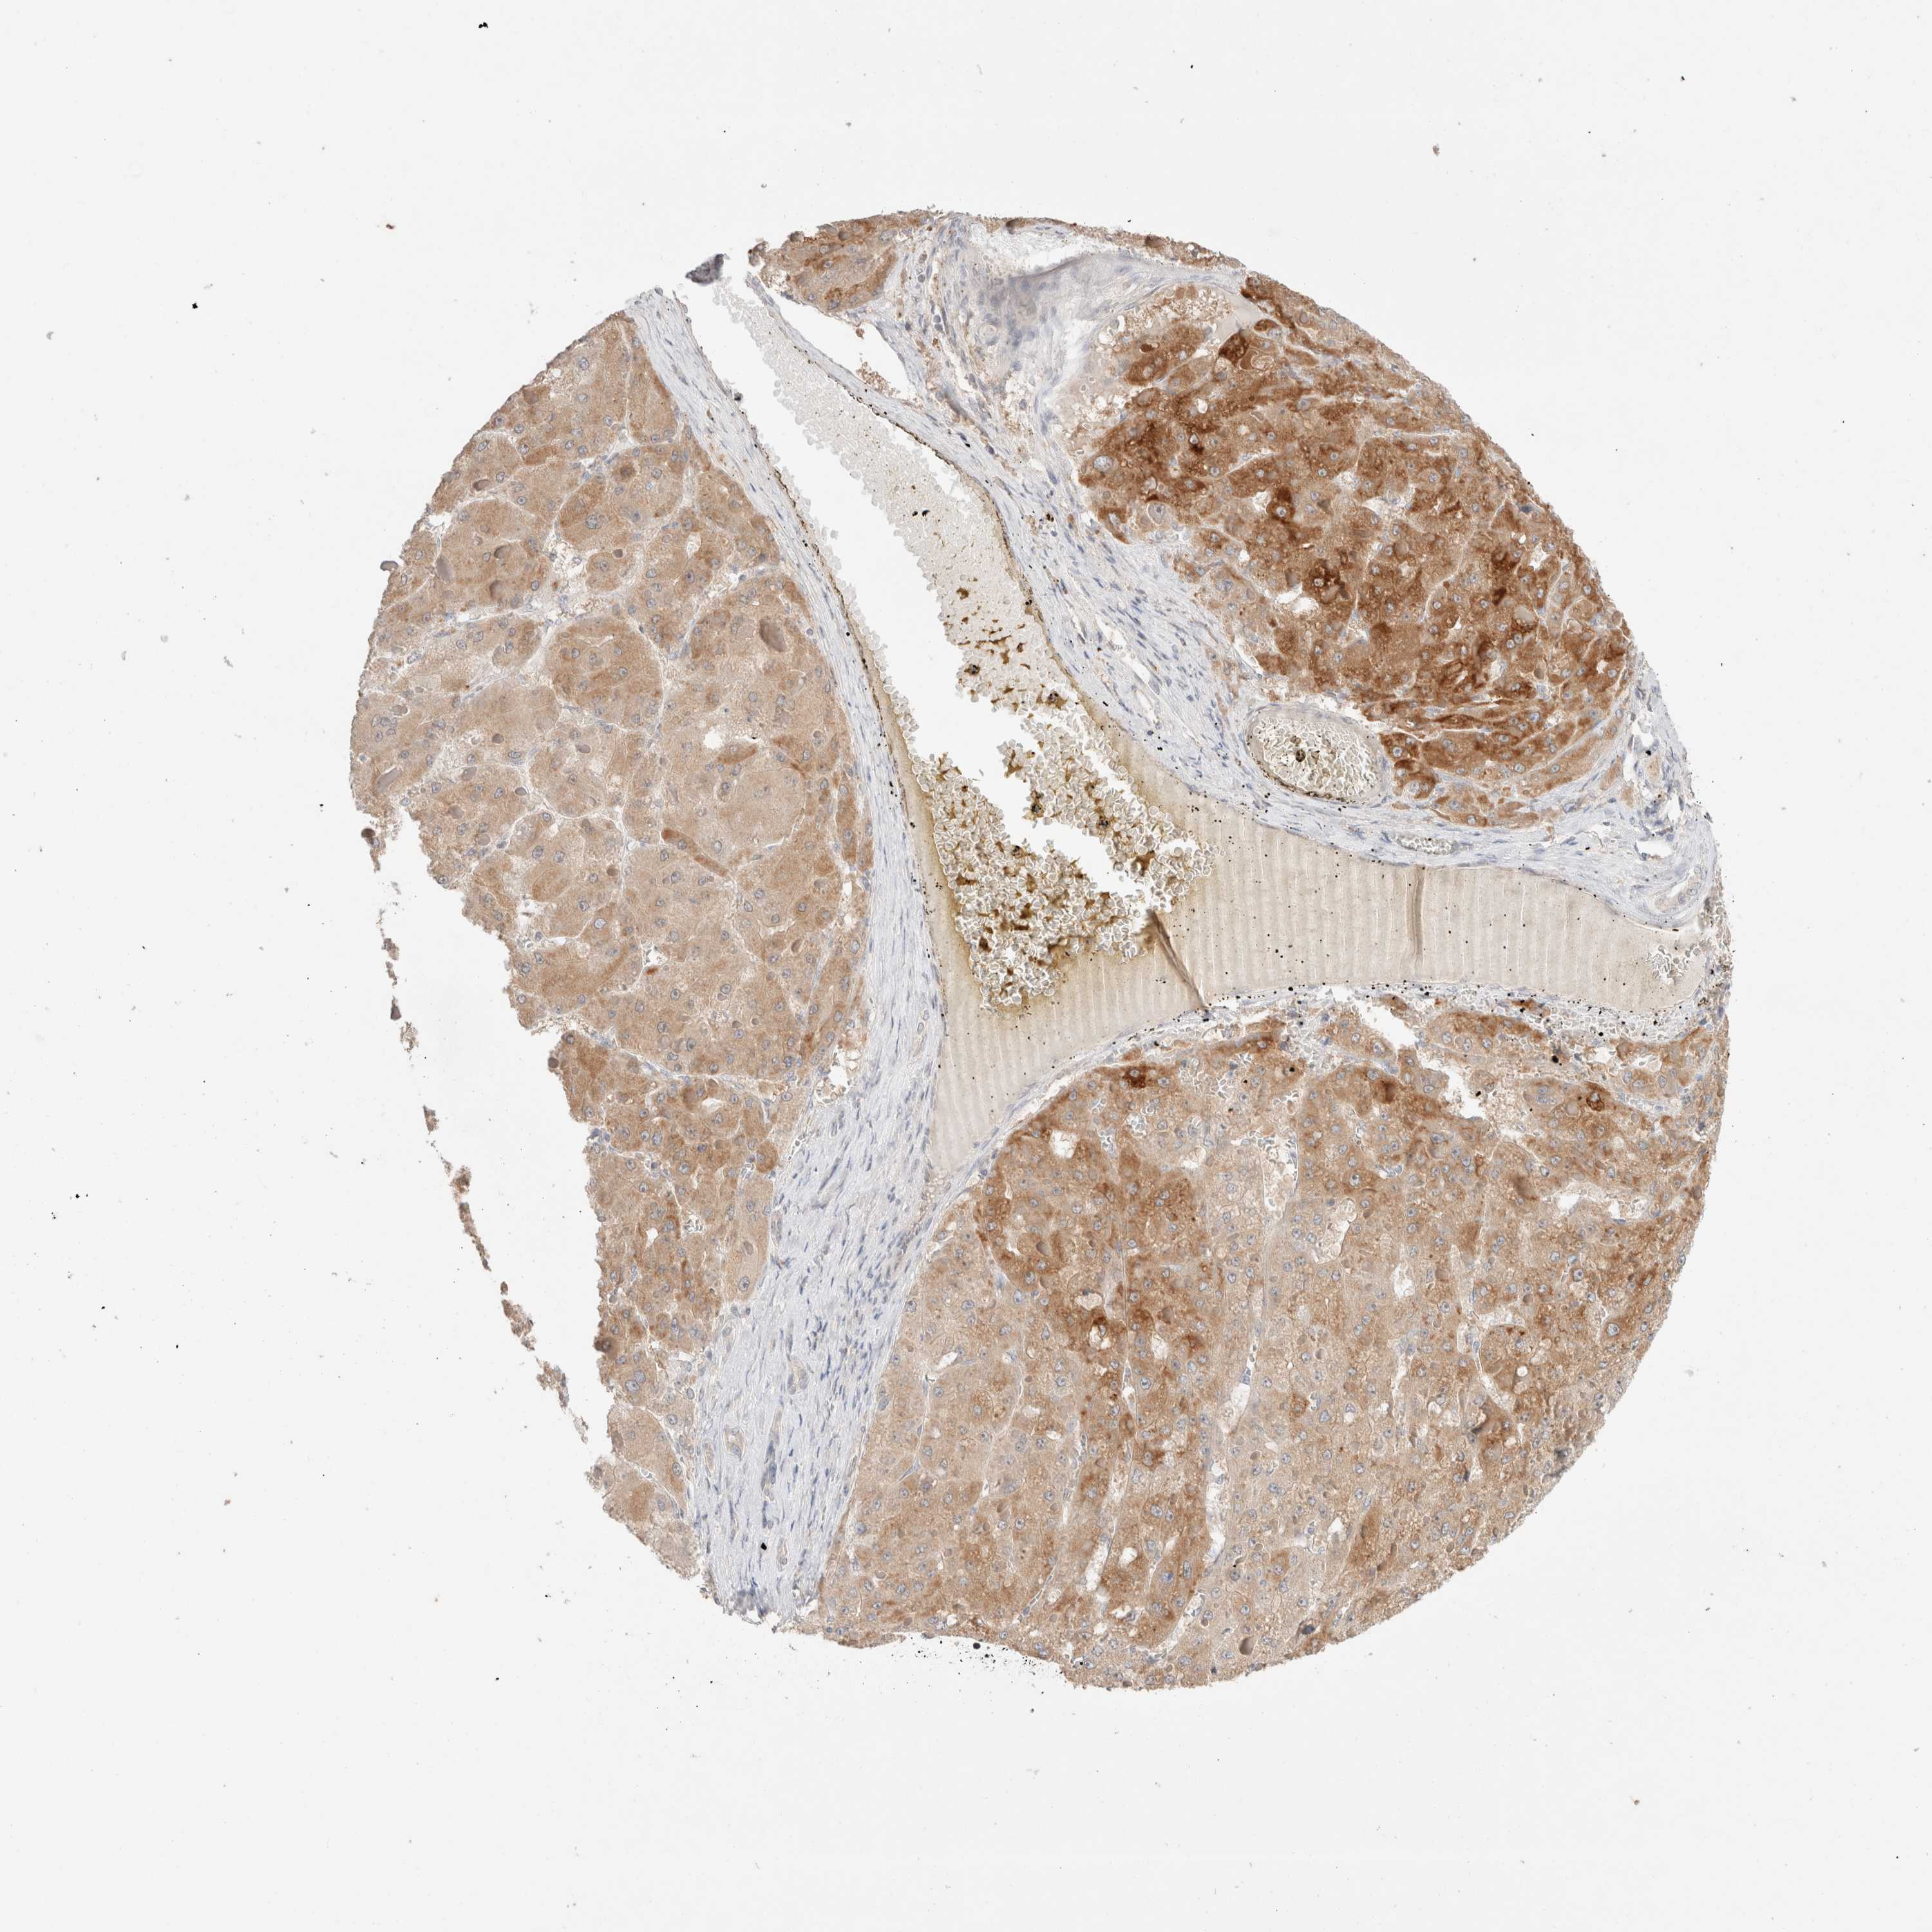

LIVER CANCER - Protein expressioni

A mouse-over function shows sample information and annotation data. Click on an image to view it in a full screen mode. Samples can be filtered based on level of antibody staining by selecting one or several of the following categories: high, medium, low and not detected. The assay and annotation is described here.

Note that samples used for immunohistochemistry by the Human Protein Atlas do not correspond to samples in the TCGA dataset.

Antibody stainingi

Antibody staining in the annotated cell types in the current human tissue is reported as not detected, low, medium, or high, based on conventional immunohistochemistry profiling in selected tissues. This score is based on the combination of the staining intensity and fraction of stained cells.

Each image is clickable and will lead to virtual microscopy that enables deeper exploration of all samples and also displays staining intensity scores, fraction scores and subcellular localization as well as patient and tissue information for each sample.

Antibody HPA024204

Staining

High

Medium

Low

Not detected

Intensity

Strong

Moderate

Weak

Negative

Quantity

>75%

75%-25%

<25%

None

Location

Nuclear

Cytoplasmic/membranous

Cytoplasmic/membranous,nuclear

Cholangiocarcinoma

Carcinoma, Hepatocellular, NOS